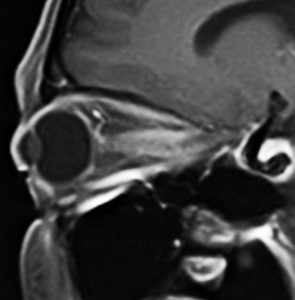

視神経鞘髄膜腫 optic sheath meningioma

眼窩内腫瘍です。視神経を包むし神経鞘から発生して,視神経鞘に沿って進展して増大します。視神経を圧迫してゆっくり症状が出ます。片目の視力が落ちるというのが症状ですが気づかれず発見が遅れることが多いでしょう。眼底検査で,初期には視神経乳頭 optic discの腫れが見られ,視力が悪化していくと視神経萎縮となります。眼底検査で動静脈シャントが見られるのも特徴的で,視力低下と視神経萎縮と併せてHoyt-Spencer triadと言われました。視力がほぼ消失するまで腫瘍が増大すると,眼球が前に押されて,眼球突出 exophhalmus, enophthalmus という症状が出ます。

治療は手術摘出ですが,この腫瘍を摘出するとほぼ確実に片眼の視力を消失します。ですから視力が無くなるまで手術は待機するという考え方が一般的です。数年以上視力があまり低下しないで腫瘍も増大せず経過する患者さんもいます。視力温存目的で治療するなら,視力の良いうちに定位放射線治療を行うべき疾患です。だからといって何でも定位放射線治療をすればよいというものではありません。問題は,視神経管から鞍結節に腫瘍が伸展している例があるということです。ここを放置すると反対側の健常な眼の視力が侵されることになりかねないので慎重に判断します。

比較的急速に視力低下して手術摘出した例

右目が暗いという症状で発症して,眼科では視神経乳頭腫脹とわずかな視野欠損だけで発症した患者さんです。3年間観察されましたが,その間には眼底所見も視力 Vd 1.2 も変化がなかったとの眼科からの報告です。そのすぐ後で患者さん本人は,右目が暗くなる回数が増え、視野狭窄があり軽い眼球突出,まわりがぼやけてますが中心は1.0見える状態との訴えで相談を受けました。主治医の先生の方針では経過観察ということで,まだ視力も良いので私もそうした方がよいと同意したのですが,その後半年くらいで視力が手動弁まで低下してしまいました。眼球運動と右眼球を温存するために腫瘍を摘出しました。

左側は,摘出標本の輪切りの写真です。この部位は腫瘍の発生した部位ではありません。一番外側にみえるのは視神経鞘 optic sheathという膜です。その内側が髄膜腫で,その内側が視神経です。すなわち髄膜腫は,視神経鞘と視神経の間のくも膜下腔を,這うように伝わって増殖伸展しています。このくも膜下腔には視神経への栄養動脈や網膜動脈も入っているので,この腫瘍だけを視神経や細動脈を傷つけずに摘出することはできないのです。